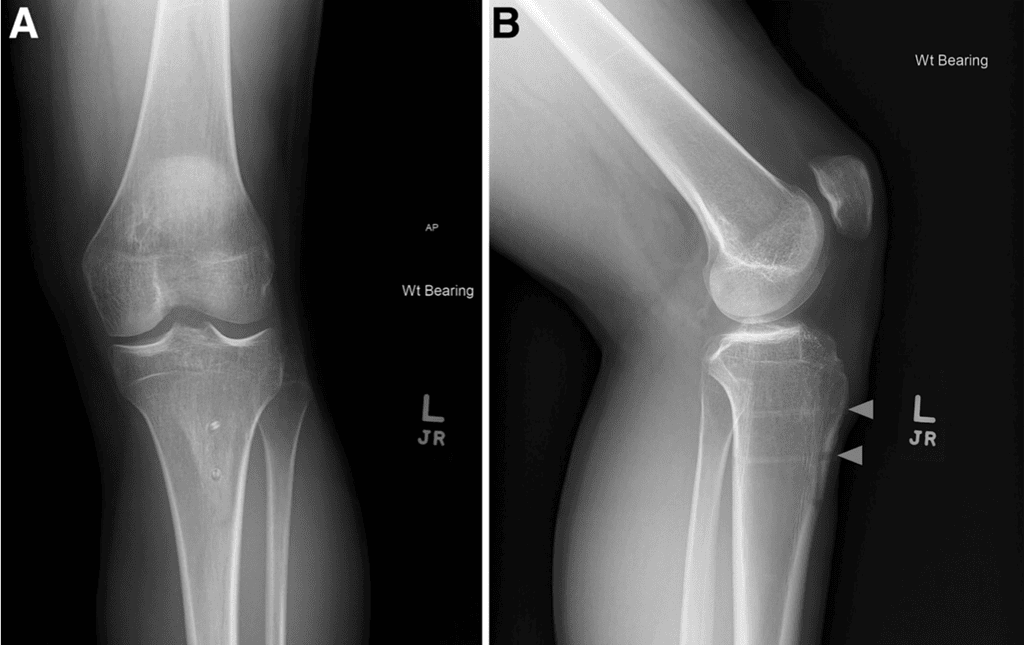

The patient was placed supine on a standard operating room table. Diagnostic arthroscopy was performed before TTO and intraarticular pathology was treated at that time. For TTO, an 8-cm longitudinal incision was made centered over the tibial tubercle to identify and free the medial and lateral borders of the patellar tendon. The anterior compartment was elevated from the lateral tibia using a Cobb elevator to expose the osteotomy site. A freehand cut at 10-15° was made from medial to lateral across the tibial. The periosteum was left intact at the distal osteotomy and straight osteotomes were used to complete the superomedial and superolateral portions of the osteotomy before completing the distal aspect of the osteotomy. The tibial tubercle was medialized approximately 9 mm, then secured with 2 Kirschner wires at the desired screw location and trajectory. The superior screw path was drilled, then length was measured, and finally tapping and countersinking were performed before metal or bio-integrative screw placement (Figure 1). This process was repeated for the inferior screw and verified under fluoroscopy. For the biointegrative screws, any remaining screw prominence was able to be removed with rongeur until flush with the tibia tubercle. No bone grafting was performed at the osteotomy site.

Figure 1: After tibial tubercle osteotomy (red arrowheads), anteromedialization was held in place with 2 Kirschner wires (A) for cannulated drilling (B) as shown on lateral fluoroscopy of the knee with the patient in the supine position. Tapping of each screw tract was performed (C) for biointegrative compressive screw placement for fixation. After placement, 2 radiolucent tracks can be seen at the site of the inferior and superior biointegrative screws (D).